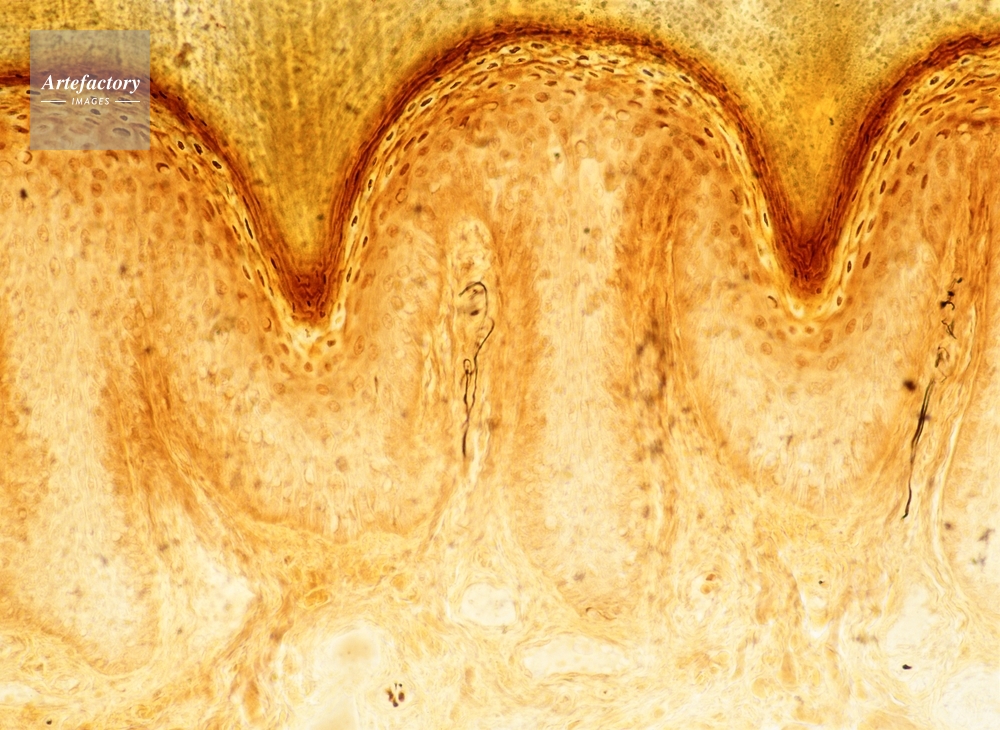

| 作品タイトル | マイスナー小体・ヒトの指(染色) | モデルリリース | なし | |

| キャプション | 長辺55mmの場合、100倍 | 制限事項 | ||